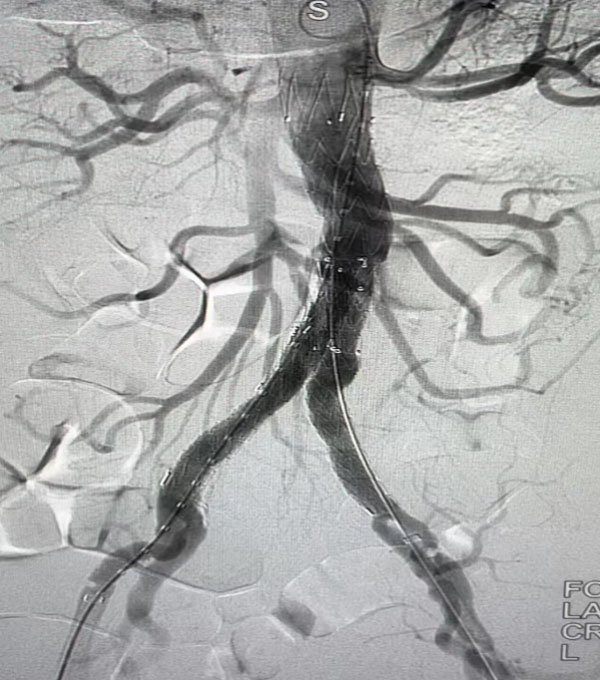

同期另一台升主动脉置换+全主动脉弓置换+胸主动脉覆膜支架腔内隔绝术”正在开展,该病例为一名A型主动脉夹层患者。在主动脉弓及分支成功游离心脏停跳后,心外科负责人赵永波转场为患者完成了血管置换,心脏复跳成功,止血彻底随后谈凌凌主治医师、侯五辉主治医师为患者进行胸主动脉腔内修复。下午2点左右台手术成功结束。通过现场视频直播,手术同时,手术人员与大会现场的专家就影像评估、手术策略、手术器械的选择及操作技巧等多个环节进行了互动讨论,学术气氛热烈,大会主席及与会代表给予我院高度评价。紧接着,手术团队又一名79岁腹主动脉瘤患者进行了腹主动脉腔内修复手术,效果良好,同样受到与会专家的好评。

腹主动脉腔内隔绝